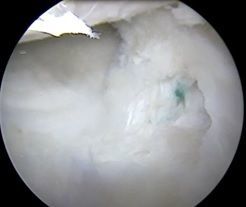

![]() ![]() | ![]() ![]() | ![]() ![]() |

| 滑膜増生を認める | 大腿骨の軟骨損傷に対して処置 | 前回手術の半月板縫合糸と半月板断裂、滑膜増生 |